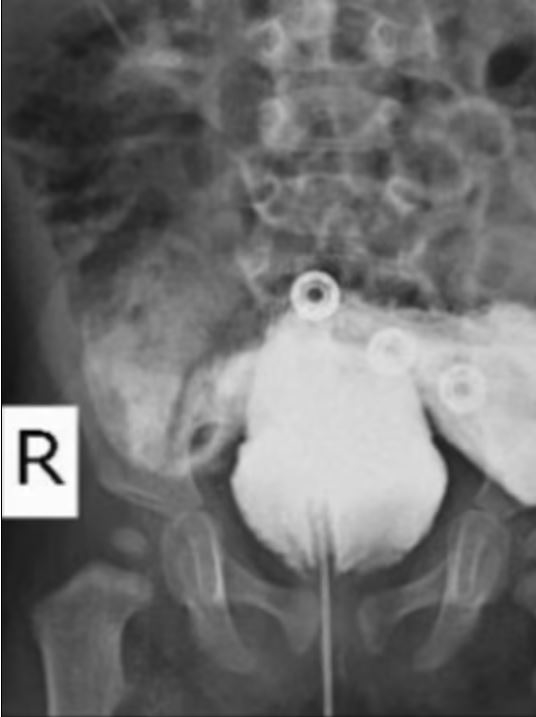

Özel bir boya ile mesane ve rektum arasındaki işlev incelendiğinde, bu iki organ arasında anormal bir bağlantı sağlayan bir fistülün bulunduğu belirlendi. Günümüzdeki cerrahlar ise; "falloplasti" ameliyatı adı verilen bir prosedürle, bu şartlar altında doğan erkek bebeklere yapay şekilde genital organları yapılıyor. Ayrıca Doktorların üriner sistemlerini tekrar birbirine bağlamasıyla onlara bir üretra da verilebilir.